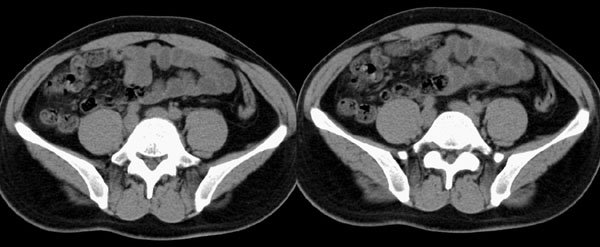

m29y平常体健,无明显不适。单位体检时发现左肾区病变。来我院作ct如下(病人不做增强):

左侧输尿管冠、矢状重建: